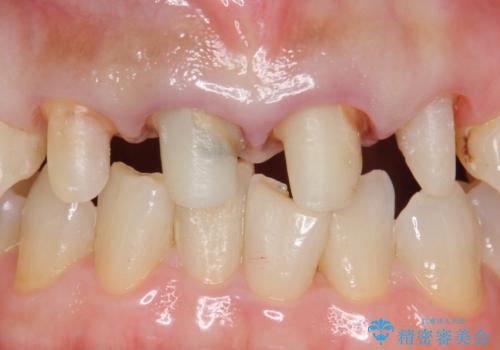

自然な前歯にしたい ジルコニアクラウンでの修復

- 前歯を綺麗にしたいとのことで来院されました。

色調・適合ともに改善するために一度被せ物を外し、歯の形を整えた後に新しい被せ物を装着していきます。

歯ぐきの炎症を抑えつつ、被せ物と歯との境目がわからなくなるよう被せ物を装着しました。

審美性が大変改善されたことで患者様にもご満足いただけました。